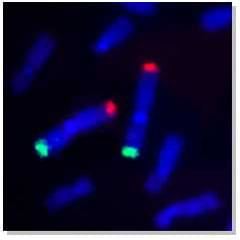

Próbki sond FISH:

Sonda do malowania ludzkiego chromosomu 1 (zielony) |

Sonda do malowania ramienia ludzkiego chromosomu 1 |

Sonda do malowania końcówek ludzkiego chromosomu 1 |

Sonda centromeru ludzkiego chromosomu 3 |

Ludzki chromosom e 1 sondy subtelomerowe |

Sygnał hybrydyzacji ludzkiej sondy genowej XIST ( czerwony) |